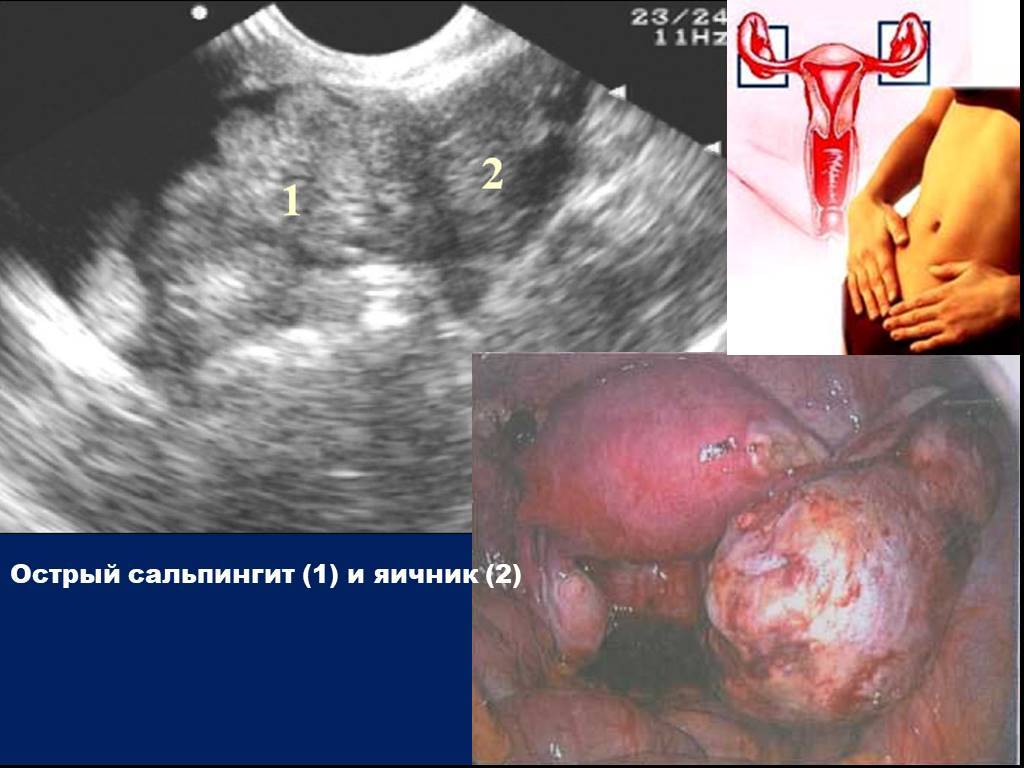

- УЗИ органов малого таза и женской половой сферы. Они позволяют определить, насколько увеличены яичники, есть ли признаки утолщения маточных труб.

- Лапароскопия. Назначается, если женщина не может долго забеременеть, несмотря на регулярную половую жизнь. Этот способ позволяет установить, какая проходимость маточных труб, есть ли спайки. Лапароскопия применяется для наиболее точного определения диагноза при невозможности получения результатов обследования другими методами.

Особенности

Придатками называют яичники и фаллопиевы трубы. Воспаление труб (сальпингит), как правило, сочетается с воспалением яичников (оофоритом), поэтому процессу дали общее название сальпингоофорит. По-другому его еще называют аднекситом. Причиной воспаления придатков является проникновение в органы возбудителей различных инфекций.